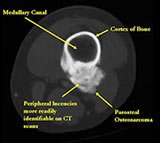

- Appears to have broad attachment to underlying cortex with a cleft between exophytic base and cortex at periphery. This is referred to as a “String Sign” (cleft is often only identifiable on CT scan)

- There may be invasion of the medullary canal with long standing disease

MRI/CT:

- Useful for determining medullary invasion